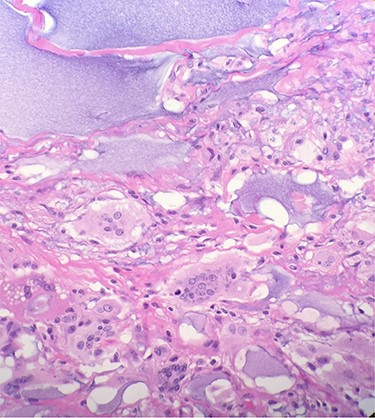

Gross pathologic examination of breast specimens demonstrated presence of pink-tan colored membranous tissue, consistent with fibrotic capsular tissue intermixed with polymers of polyacrylamide. Microscopic examination demonstrated presence of benign breast tissue with fibrosis, foreign body giant cells and chronic inflammatory cells. There was extensive purple, gelatin-like material which represented the presence of polyacrylamide hydrogel (Fig. 3).

The indication for bilateral nipple-sparing mastectomy and en bloc capsulectomy was supported by histopathological analysis of excised breast tissue which demonstrated extensive inflammation and damage at the cellular level. The foreign body reaction and chronic inflammatory infiltrate observed in our patient is in accordance with available literature which suggested the dismal biocompatibility of PAAG [4]. Our histopathological analysis is also consistent with data derived from tissue samples with PAAG by Leung et al. which demonstrated extensive foreign body reactions with profound fibrosis and inflammation [5]. Other histological findings have been described by Christensen et al., who found evidence of granuloma formation consisting of lymphocytes, foreign body cells, and macrophages surrounding locations of PAAG injection [6].

Microscopic examination reveals benign breast tissue with fibrosis, foreign body giant cells and chronic inflammatory cells (H&E 20×) Extensive, scattered, purple, gelatin-like material was also present which represents the presence of polyacrylamide hydrogel.